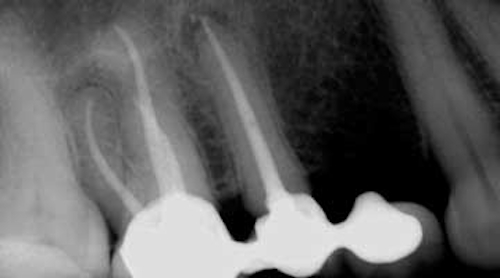

It is most important to protect against dental damage after treatment. Usually Antibiotics are not necessary after a Root Canal procedure. But if you have a huge periapical abscess pus at the root of the infected root tips then youre advised to take antibiotics so that the infection doesnt spread.

Root canal therapy is intended to treat and prevent infection of the root canal system so many patients wonder why their general dentist or endodontist does not prescribe antibiotics in addition to root canal therapy. If a patient has a significantly compromised immune system or signs of a systemic infection antibiotics are a way to give our body an edge over a potential infection. You need antibiotics and an endodontist needs to repeat the failed root canal treatment.